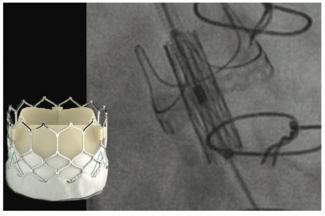

A 61-year-old man presented with progressive, limiting breathlessness. He had undergone orthotropic heart transplant 34 years prior for idiopathic dilated cardiomyopathy, subsequently requiring renal transplantation for calcineurin inhibitor...